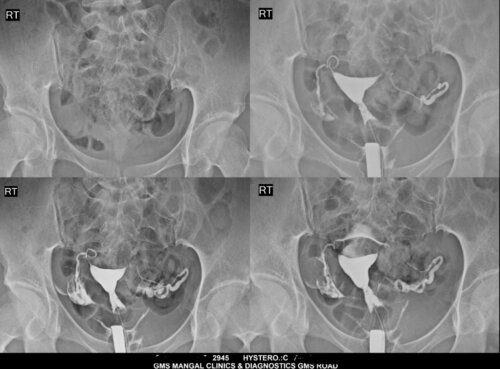

Hysterosalpingography (HSG) by Female Radiologist in Dehradun | GMS Mangal Clinic & Diagnostics

GMS Mangal Clinic & Diagnostics, under the continued expertise of Dr. Deepti Agarwal Consultant Radiologist in Dehradun, has been providin...